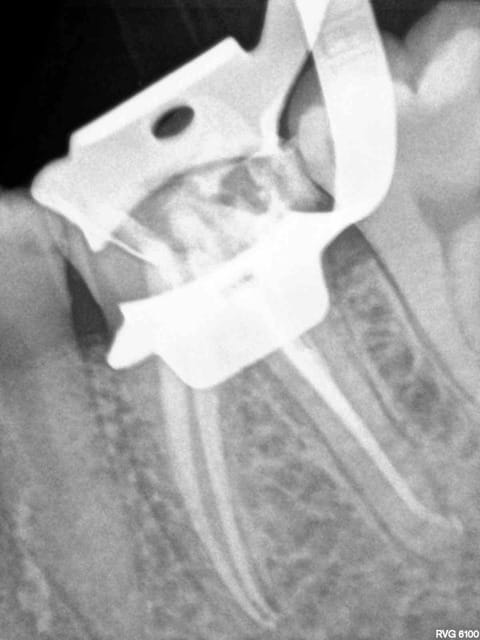

Canaux LT 25 mm. 2 récapitulations R25-S1 pour arriver au bout quand meme, mais en général pas besoin.

Radio cones en place systématiques, des fois ca dépasse d'un mm, il suffit de les couper.